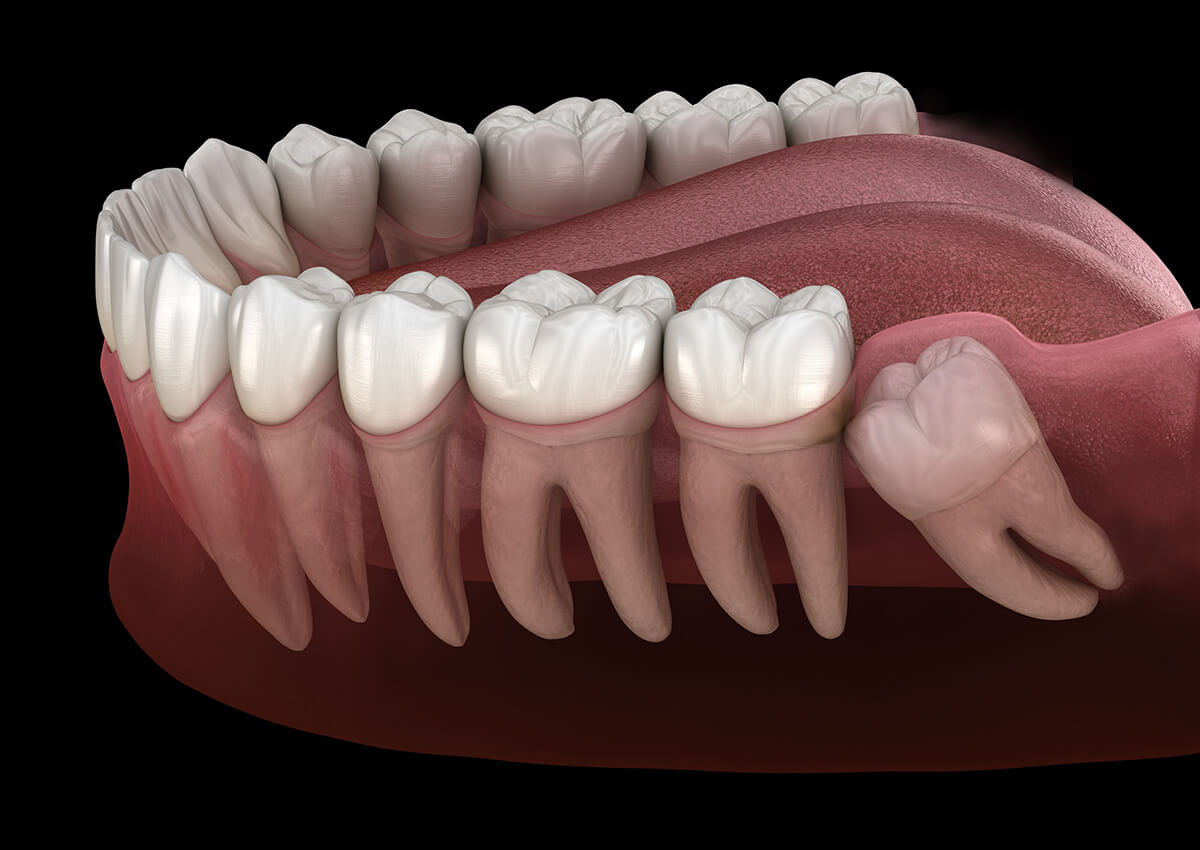

Wisdom teeth (third molars) become impacted because they don't have enough room to come in (erupt) or develop normally.

Wisdom teeth usually emerge sometime between the ages of 17 and 25. Some people have wisdom teeth that emerge without any problems and line up with the other teeth behind the second molars. In many cases, however, the mouth is too crowded for third molars to develop normally. These crowded third molars become trapped (impacted).

An impacted wisdom tooth may partially emerge so that some of the crown is visible (partially impacted), or it may never break through the gums (fully impacted). Whether partially or fully impacted, the tooth may:

tooth Grow at an angle toward the next tooth (second molar)

tooth Grow at an angle toward the back of the mouth

tooth Grow at a right angle to the other teeth, as if the wisdom tooth is "lying down" within the jawbone

tooth Grow straight up or down like other teeth but stay trapped within the jawbone